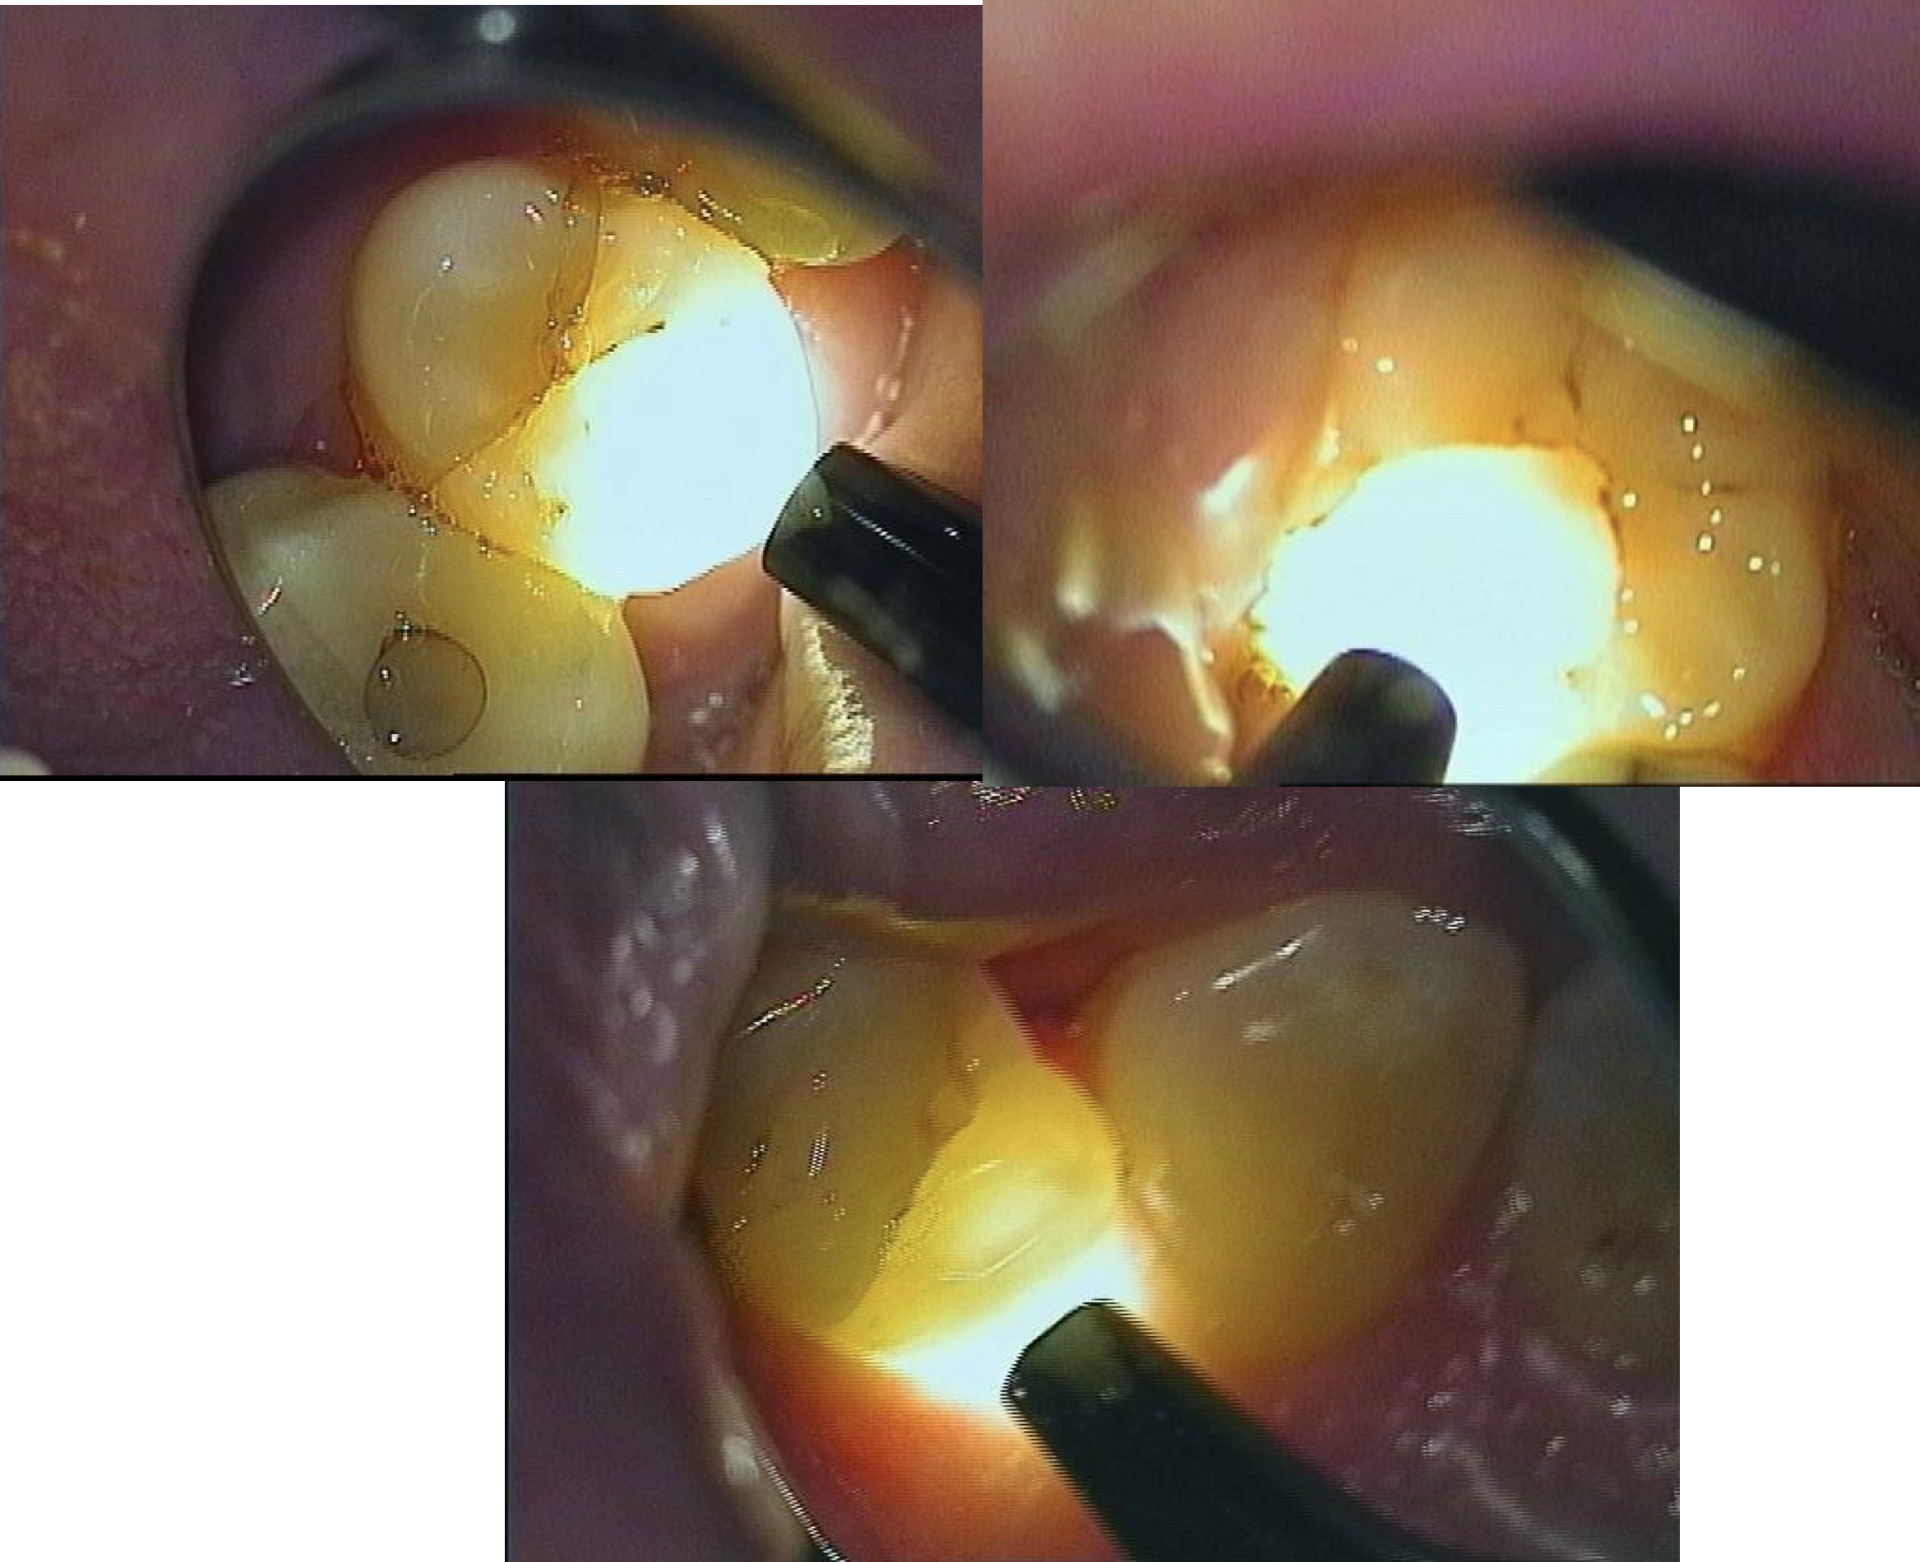

Billederne er herunder er taget fra en undervisningsvideo, hvor en plastictand slibes til af en ekspert.

En nøje undersøgelse med gennemlysning afslørede yderligere 5 tænder med revner. Kun de tre tænder fra overkæben er vist her.

Tænder undersøgt med transillumination